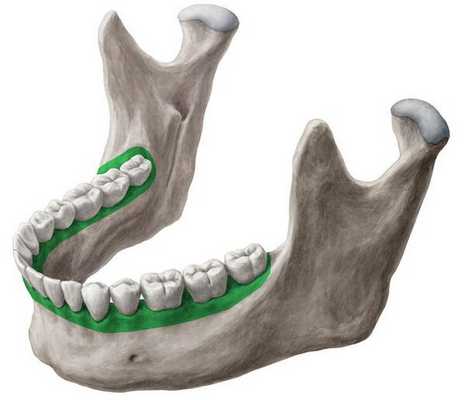

Поэтому при глубоком прикусе заметно:

- чрезмерное прорезывание передних зубов,

- в боковом отделе укорочение высоты зубов

- либо недопрорезывание боковых зубов,

- либо это сверхпрорезывание во фронтальной группе - в передней группе зубов.